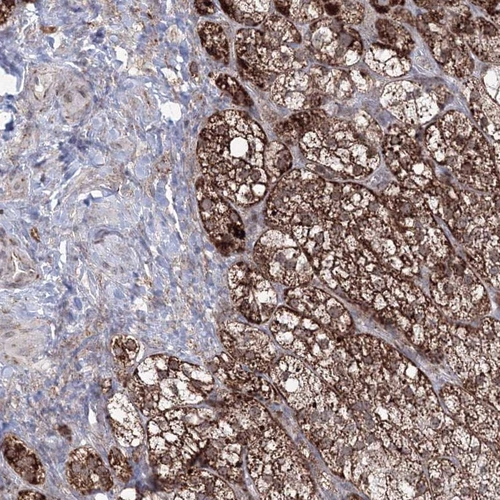

Immunohistochemistry analysis in human adrenal gland and pancreas tissues using HPA036984 antibody. Corresponding GRSF1 RNA-seq data are presented for the same tissues.